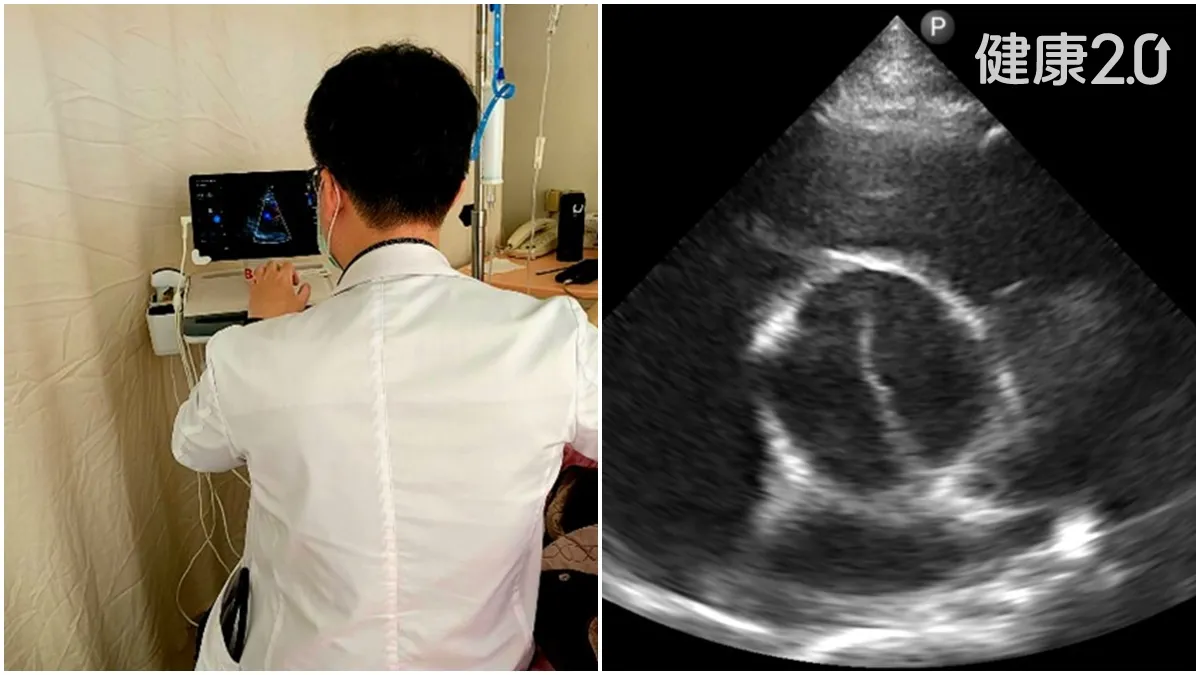

住院數小時內,主治醫師曾致學親自到病床旁,以臨床重點式超音波(POCUS)進行床邊檢查,發現江先生罹患A型主動脈剝離,伴隨嚴重主動脈瓣逆流與心衰竭徵象。曾醫師表示,主動脈剝離屬於心血管急重症,情況十分危急,需立即會同外科醫師評估緊急手術治療。

pocus是近年整合醫學的重要利器

台北榮總全人整合醫學科張景智主任表示,臨床重點式超音波(POCUS)是近年整合醫學的重要利器。它不僅能即時於床邊提供病灶影像資訊,更在心血管、胸腔、腹部等急重症狀況中發揮即刻診斷的關鍵價值。在這起案例中,曾致學醫師正是憑藉POCUS第一時間揪出致命病灶,成功讓患者重獲新生。

江先生現已恢復正常生活,持續門診追蹤及抗凝治療。他感謝曾醫師與整個醫療團隊的細心與即時判斷:「如果不是那時候做了超音波,我可能等不到手術那一刻」。張景智主任表示,全人整合醫學科身為急診病患的後送病房,同時也肩負起整合醫學照護的關鍵角色。面對病情未明、合併多重系統問題的患者,特別需要全面性臨床判斷與跨專科合作。臨床重點式超音波(POCUS)正是該科的核心診斷工具之一,讓第一線醫師能即時在病床邊掌握關鍵病灶,不放過任何一項可能威脅生命的隱性疾病。